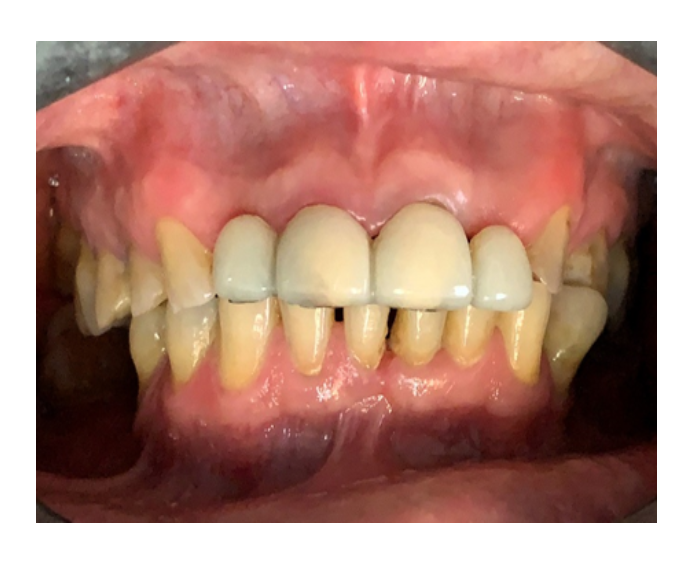

Prótesis fija de zirconia

sin metal